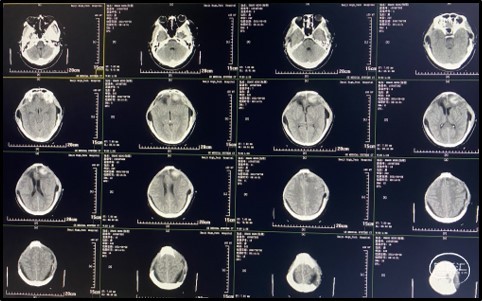

术后复查头颅CT(术后第1天)

20头颅CT提示:双侧额叶减压充分,术区未见明显出血,侧脑室引流管在位。

术后复查头颅CT(术后第3天)

头颅CT:左侧额叶少量渗血,三脑室、双侧侧脑室、环池显露良好。